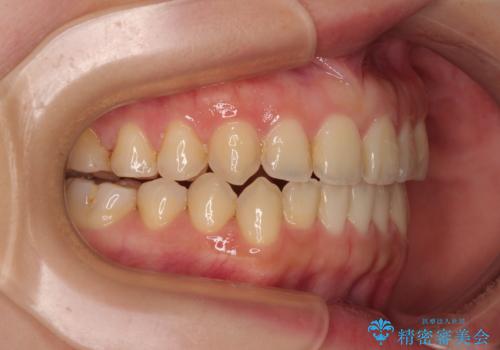

前歯のオープンバイト インビザラインで咬み合わせを改善

- 前歯の開咬を気にして来院された患者様です。

開咬の治療は、前歯を閉じるように動かすとともに、上下臼歯を圧下(骨内にめり込ませる)させることで進めて行きます。

インビザラインは臼歯の圧下を効果的に行えるため、インビザラインを用いて矯正治療を行うこととしました。